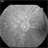

- angioid streaks

- Charlotte Harris Midwest Eye Institute Indianapolis, IN

Fundus camera

TOPCON EX - Description

- FA of a 24-year-old male with mild onset of blurry vision, angioid streaks OS>OD. Observation recommended for now.